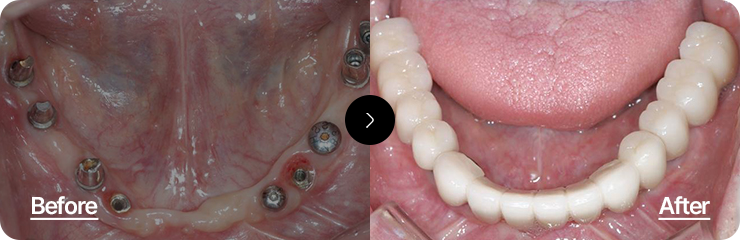

상실된 치아 전체를 복원하여

자연스럽고 건강한 구강 기능 회복

최소한의 임플란트로 최적의 위치에 식립하여 기능과 심미성을 동시에 회복하는 치료입니다.

정확한 교합 분석과 풍부한 임상 경험이 요구되는 고난이도 시술입니다.